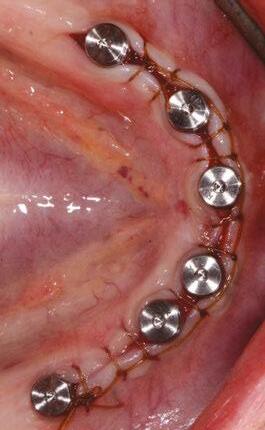

A patient presented with a failing bridge on the upper left that is supported by three mini implants. The implants directly perforate the sinus and only ~2mm of residual bone height remains on the crest (Figure 8). The mini implants were removed, and a

Figures 7A and 7B: Horizontal mattress sutures are useful for helping to secure membranes in grafting situations and relieving tension in longer span incisions Figures 8A and 8B: The pre-op condition of the patient with mini implants engaging minimal bone and perforating the sinus. The patient’s implant supported bridge was loose and causing discomfort Figure 9: A periosteal biting mattress engages only the periosteum in the buccal vestibule and exit and re-enters on the lingual tissue, helping to secure the membrane tightly over the window and crest